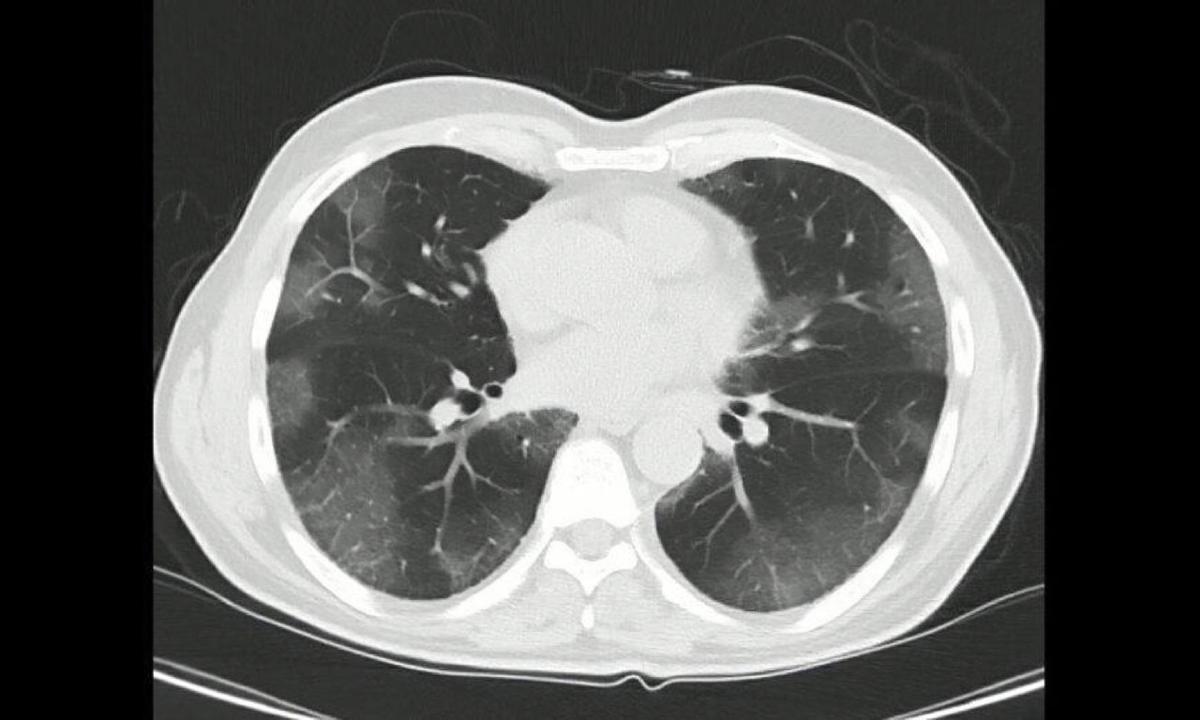

“White lung” refers to a manifestation seen on chest X-rays and CT scans in cases of severe pneumonia. For a healthy person, in a chest X-ray or CT scan, the lungs appear black because they contain air. But when the lungs are severely infected or acutely injured, the tiny air sacs (alveoli) and capillaries in the lungs are damaged, and blood and fluid leak into the spaces between the air sacs and eventually into the air sacs, causing the alveoli to collapse. This is when patchy white shadows appear on the image; the lungs appear white, hence the term white lung.When this happens, alveolar fluid builds up, and blood oxygen levels drop precipitously. When most alveoli collapse, oxygen cannot enter the bloodstream. Clinical manifestations include chest tightness, shortness of breath, poor breathing, and blood oxygen saturation of less than 93 percent. Symptoms such as cyanotic complexion (a bluish appearance), sweating, rapid heartbeat, and cognitive confusion may occur.